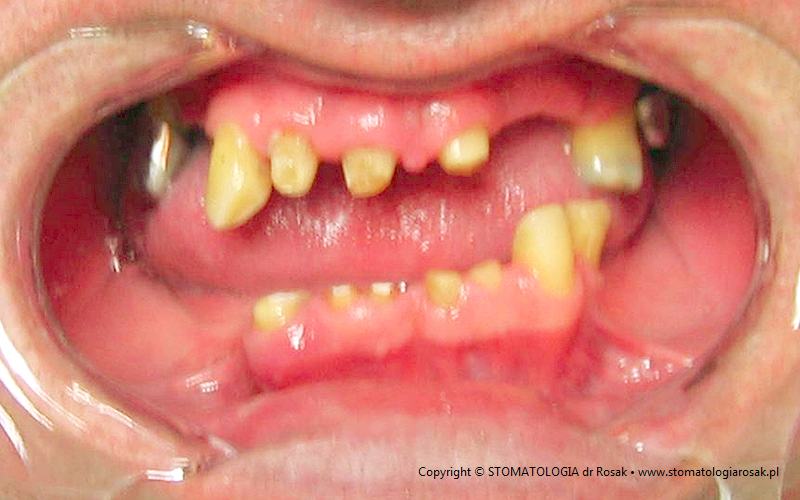

5. Pacjentka lat 18 z wrodzonym brakiem wielu zębów tzw. hipodoncją – rehabilitacja protetyczna z wykorzystaniem

stałych mostów porcelanowych na podbudowie metalowej.

| 5a. Stan przed leczeniem |

5b. RTG panoramiczne |

| 5c. Uzupełnienia tymczasowe na okres leczenia |

5d. Próba struktury metalowej mostu porcelanowego górnego |

| 5e. Gotowy most porcelanowy górny i próba struktury metalowej dolnej |

5f. Gotowe mosty porcelanowe |